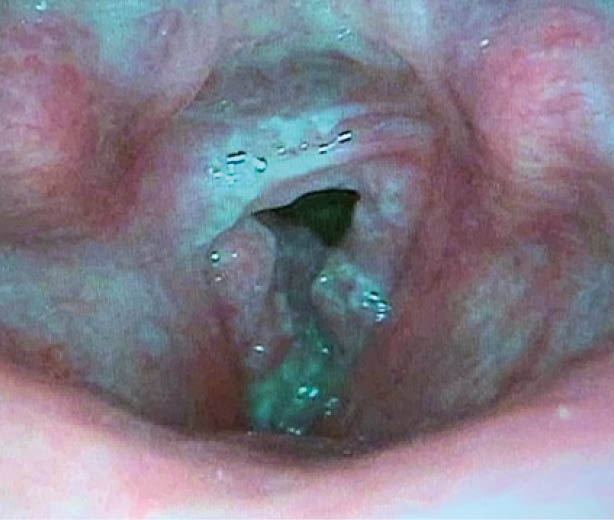

Stimmlippenkarzinom (Abb. 2):

Hier würde man eher eine kürzere Symptomdauer von 2-4 Monaten erwarten. Es wäre jedoch auch eine Entartung auf Grund einer chronischen Laryngitis mit somit längerer Anamnese möglich. Bei Stimmlippenkarzinomen ist eine Früherkennung durch eine rechtzeitige Laryngoskopie wichtig und auch möglich, da sich bereits kleine Stimmlippenkarzinome meistens rasch durch Heiserkeit manifestieren. In frühem Stadium kann eine günstige Prognose durch alleinige mikrolaryngoskopische Resektion oder primäre kleinvolumige Bestrahlung erwartet werden.